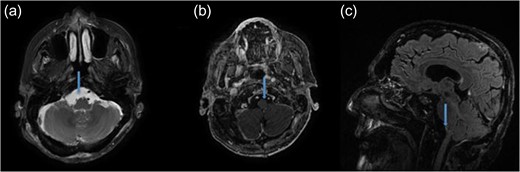

A 68-year-old male presented with 10-pound weight loss over the course of the last month as a result of progressive difficulty with swallowing. The neurological examination revealed a diminished gag and a weak cough reflex. His tongue was deviated to the right with significant atrophy. MRI of the head revealed a heterogeneous, contrast-enhancing mass that was hypointense on T1 and isointense on T2-weighted images. It was 3.7 cm in diameter, located at right anterolateral part of the FM, compressing the medulla oblongata, extending into the hypoglossal canal and jugular foramen, and encasing the posterior inferior cerebellar artery (PICA) (Fig. 1).

Preoperative MRI demonstrating an anterolateral right foramen magnum mass. (a) Axial T2-weighted MRI. (b) Axial T1-weighted contrast enhanced MRI. (c) Sagittal T1-weighted contrast enhanced MRI. (d) Axial CT image of brain shows no bone sclerosis or destruction.

Gadolinium-enhanced brain MRI is the gold standard to diagnose FM metastases [6]. The FM metastases show hyperintensity on T2 and hypointensity on T1 with variable contrast-enhancement. CT is also important to show bone destruction or sclerosis especially for prostate adenocarcinoma [6]. Interestingly, FM metastases can mimic subdural hematoma and meningioma [1, 9]. With the current case no bone invasion was detected by CT scans. Radiologically our case was similar to meningioma regarding the following features: isointensity on T2, hypointensity on T1 in MRI and no bone destruction or sclerosis in CT images (Fig. 1).